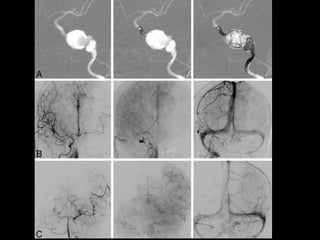

Aneurysm

Endovascular Treatments of Intracranial

Aneurysms

3-Endosaccular Embolization :

a) Technique

b) Complications

a) Technique :

-Coil embolization is performed under general

anaesthesia so the patients can be adequately

monitored and immobilized

-Selective catheterization of the aneurysm sac is

performed after systemic anticoagulation (by bolus

injection or infusion of heparin) and packing is

usually performed by placing large initial coils into

which smaller coils are packed

5-Adjuvant Endovascular Treatments :

-Coil embolization for a minority of aneurysms isn’t

possible because of their anatomy

-The features that make a particular aneurysm

uncoilable are :

a) Wide neck

b) Extreme size

c) Branch arteries arising from within the sac

d) Fusiform shape

-Stent & Coils and Flow Diverters

b) Balloon-Assisted Coiling :

-Balloon-assisted coiling (BAC) which is also known

as (the remodelling technique) involves

placement of a suitably sized compliant balloon

across the aneurysm neck during coil deployment

, the balloon is used to retain coils within the

aneurysm to compress their profile at the neck

(i.e. remodelling) and to be available to arrest

blood flow should rupture occur during

embolization

c) Flow Diverters :

-Flow diverters have been developed to treat

intracranial aneurysms

-These endovascular devices are placed within

the parent artery rather than the aneurysm

sac

-They take advantage of altering hemodynamics

at the aneurysm / parent vessel interface

resulting in gradual thrombosis of the

aneurysm occurring over time